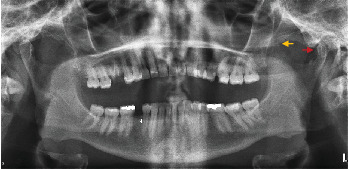

冠突的大小变化,由于增生或发育不全,可能会干扰正常的张嘴范围。摘要冠状突增生症是一种罕见的口腔颌面疾病,由于下颌冠状突的异常延长与颧弓的撞击,导致开口逐渐受限。这种情况提出了临床挑战,由于其非特异性性质的投诉,目前在患者。它的特点是逐渐无痛地限制张嘴。目前,确切的病因仍然没有定论;然而,遗传、激素、炎症或创伤的影响也有报道。在本文中,作者提出了两个病例报告的成年人怀疑单侧创伤后冠状增生和发育性髁发育不全,有历史的物理创伤造成的青春期。提供了一份简明的文献更新,以强调病因,准确诊断的意义,以及在恢复功能和美学方面实现有利结果的量身定制的治疗方式。

Changes in the size of the coronoid process, due to hyperplasia or hypoplasia, may interfere with the normal range of mouth opening. Coronoid hyperplasia is a rare oral and maxillofacial disease which might result in progressive limitation of mouth opening due to the impingement of an abnormal elongated mandibular coronoid process on the zygomatic arch. This condition presents with clinical challenges due to its nonspecific nature of complaints that present in patients. It is characterized by gradual painless restriction of mouth opening. Currently, the exact etiopathology still remains inconclusive; however, genetic, hormonal, inflammatory, or traumatic influences have been reported. In this paper, the authors present two case reports of adults with suspected unilateral posttraumatic coronoid hyperplasia and developmental condylar hypoplasia that have a history of physical trauma inflicted during adolescence. Provided is a succinct update of literature to highlight the etiopathogenesis, significance of accurate diagnosis, and tailored treatment modalities in achieving favorable outcomes to restore function and esthetics.